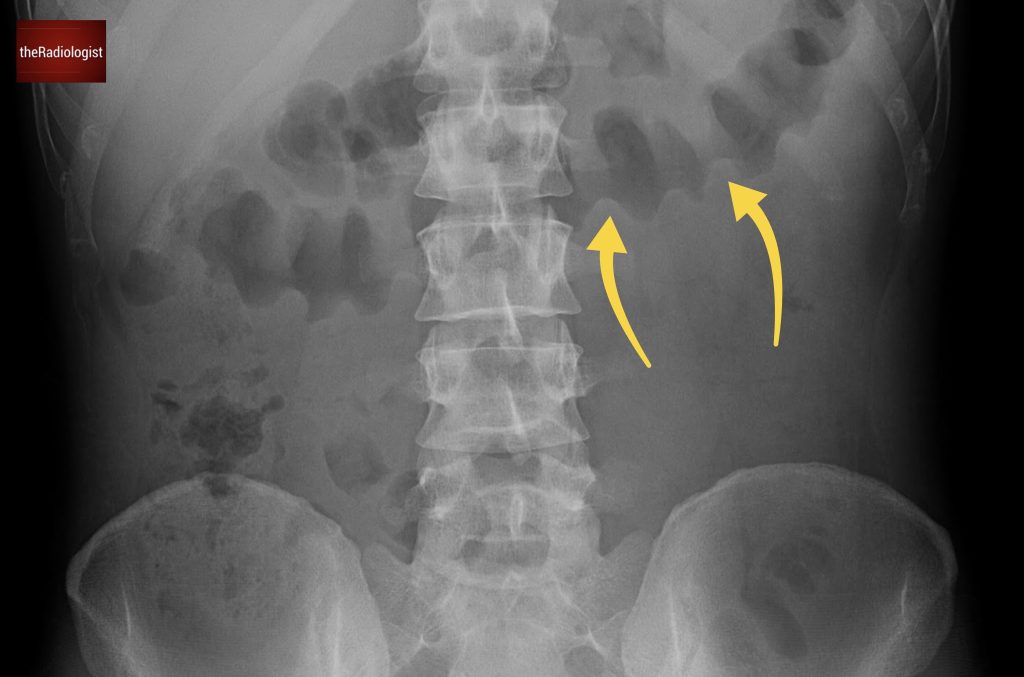

Also as we scroll down we can see there is fat stranding surrounding the psoas muscle extending into the pelvis.

There is fat stranding surrounding the psoas extending into the pelvis.